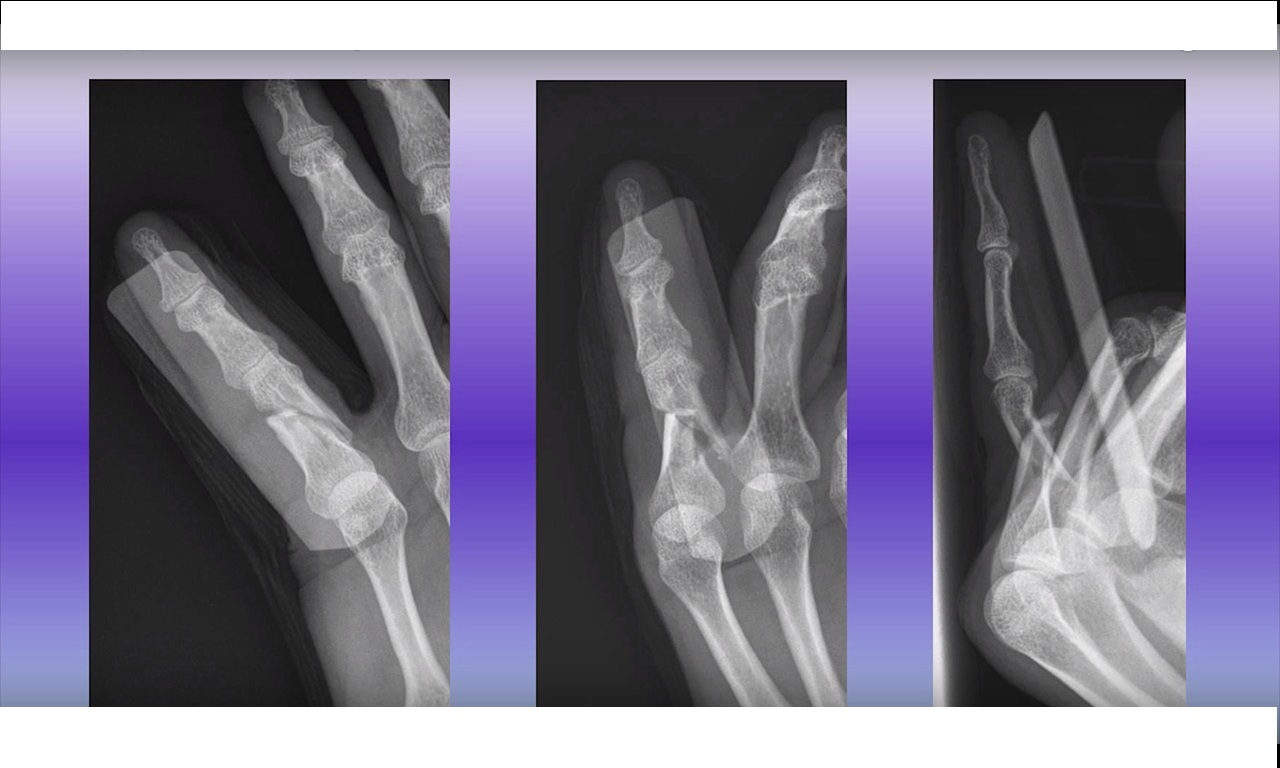

Radiological Evaluation

Plain radiography is the most important investigation for diagnosing proximal interphalangeal joint injuries.

Recommended Radiographic Views

Radiographs should be taken of the specific injured finger, rather than the entire hand.

Required views include:

-

Anteroposterior view

True lateral view

Oblique views

Multiple lateral views may sometimes be necessary to identify subtle subluxations or fractures.

Computed tomography is rarely required when properly positioned radiographs are available.

Importance of Proper Radiographs

Standard hand radiographs may be inadequate.

Essential imaging includes:

True lateral radiograph of the injured finger

Properly positioned views for accurate fracture assessment.